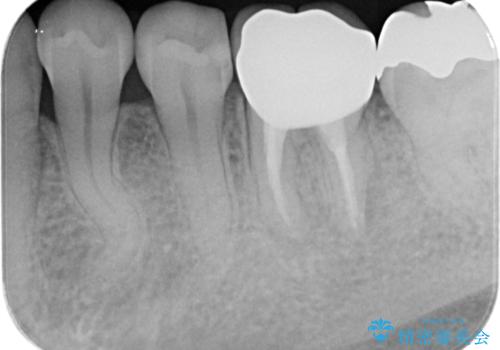

不十分な根管治療も精密根管再治療を行ったのち、精度の高いジルコニアセラミッククラウンで食べ物の詰まらない歯の形態へと改善していきます。

食事のたびに感じていた煩わしい思いから解放され、また大きく目立っていた銀歯も審美的に白く改善し満足いただくことができました。